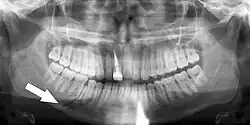

Panoramic radiograph of a simple mandible fracture of the right mandibular body, minimally displaced. Note that the teeth to the left of the fracture do not touch -

Panoramic radiographs are tomograms where the mandible is in the focal trough and show a flat image of the mandible. Because the curve of the mandible appears in a 2-dimensional image, fractures are easier to spot leading to an accuracy similar to CT except in the condyle region. In addition, broken, missing or malaligned teeth can often be appreciated on a panoramic image which is frequently lost in plain films. Medial/lateral displacement of the fracture segments and especially the condyle are difficult to gauge so the view is sometimes augmented with plain film radiography or computed tomography for more complex mandible fractures.